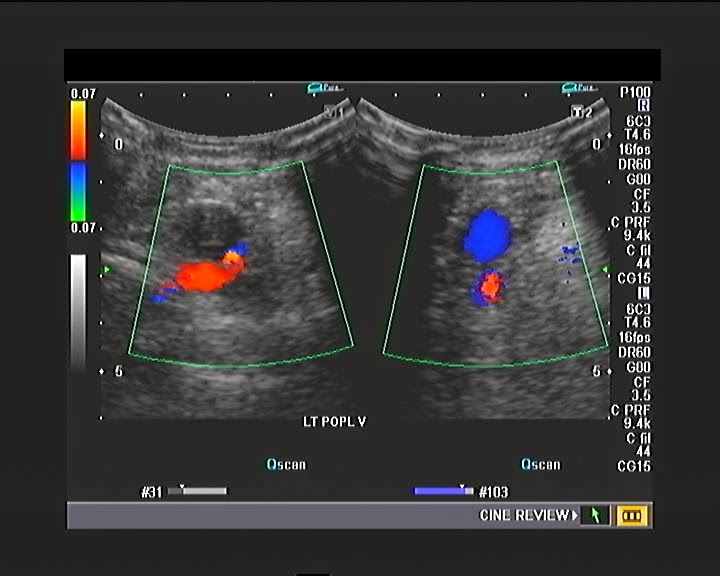

Dual screen ultrasound Bmode images of the tibial and calf veins were Calf Ultrasound Image (1) there is a well localised hypoechoic collection (c) interposed between the medial head of the gastrocnemius. The differential diagnosis in patients with calf and posterior ankle pain can span traumatic, metabolic, infectious and inflammatory,. Mskus proves a useful tool to assist the clinician. Here’s a detailed look at the different. Several imaging techniques are widely available, with ultrasonography (us). Calf Ultrasound Image.

Ultrasound image of the left mid calf with color doppler shows multiple Calf Ultrasound Image Serial longitudinal images of the calf: (1) there is a well localised hypoechoic collection (c) interposed between the medial head of the gastrocnemius. The differential diagnosis in patients with calf and posterior ankle pain can span traumatic, metabolic, infectious and inflammatory,. Several imaging techniques are widely available, with ultrasonography (us) and magnetic resonance (mr) imaging currently the most frequently applied. Calf Ultrasound Image.

A patient of calf and leg pain venous Doppler study Ultrasound Cases Calf Ultrasound Image Several imaging techniques are widely available, with ultrasonography (us) and magnetic resonance (mr) imaging currently the most frequently applied in sports medicine. Mskus proves a useful tool to assist the clinician. Here’s a detailed look at the different. (1) there is a well localised hypoechoic collection (c) interposed between the medial head of the gastrocnemius. We outline common abnormal conditions. Calf Ultrasound Image.